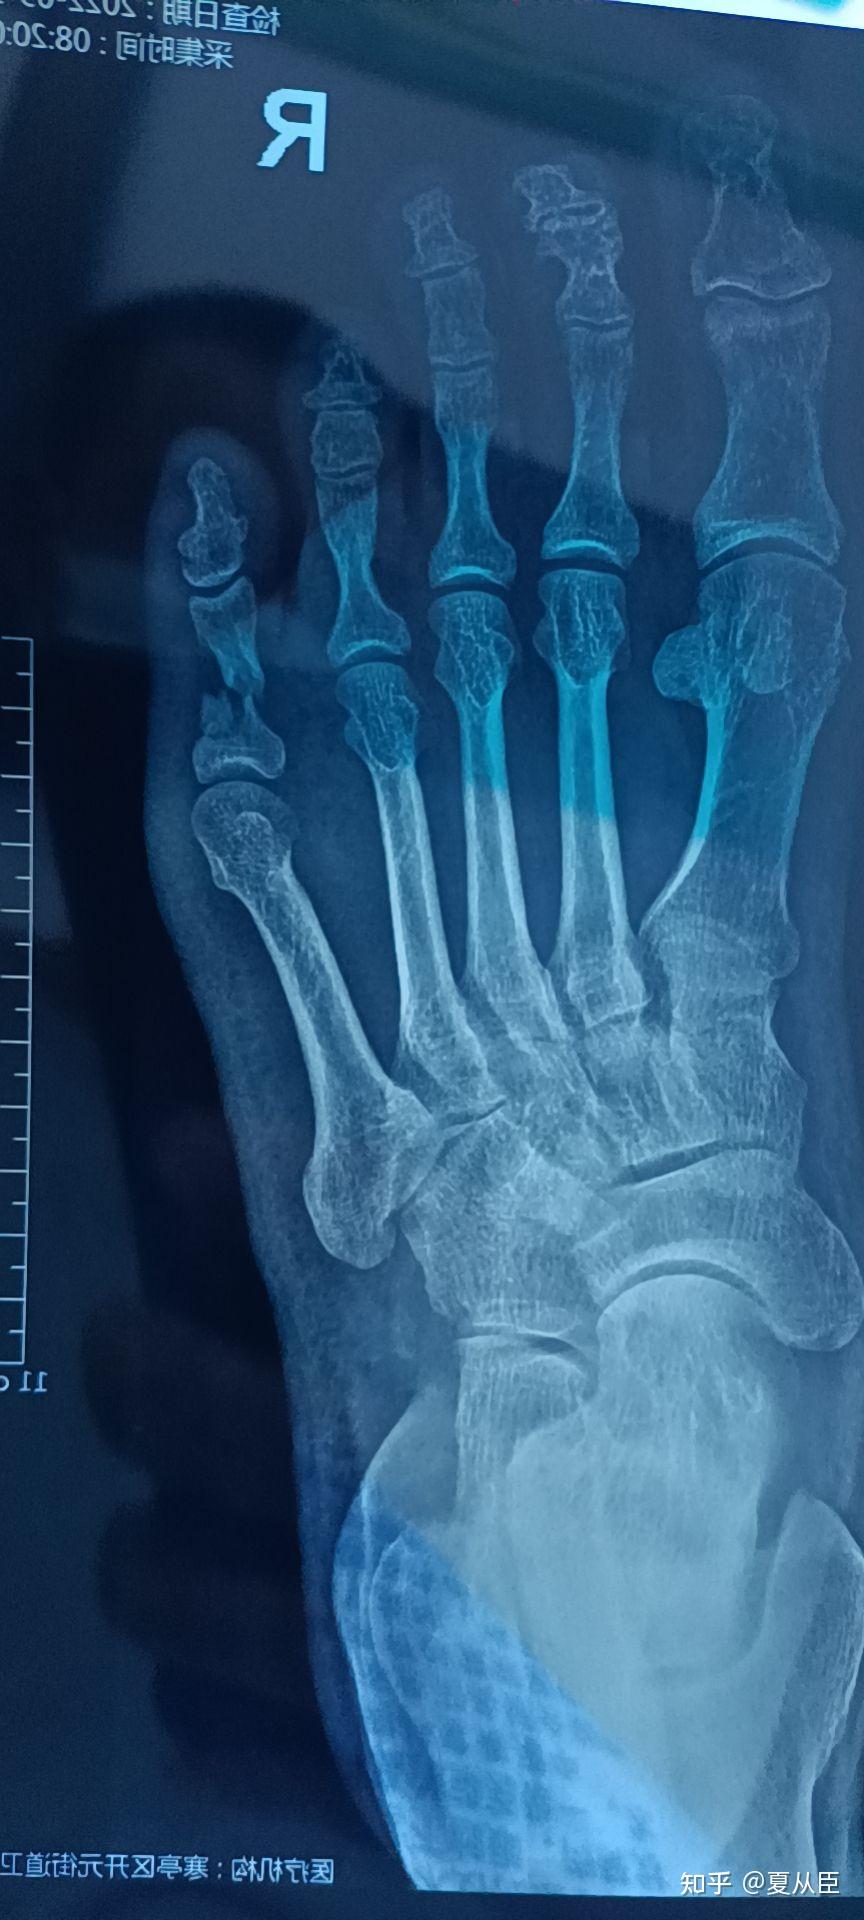

右足第3,4,5趾骨骨折-病例讨论-唯医,allinmd

图片尺寸1440x1080